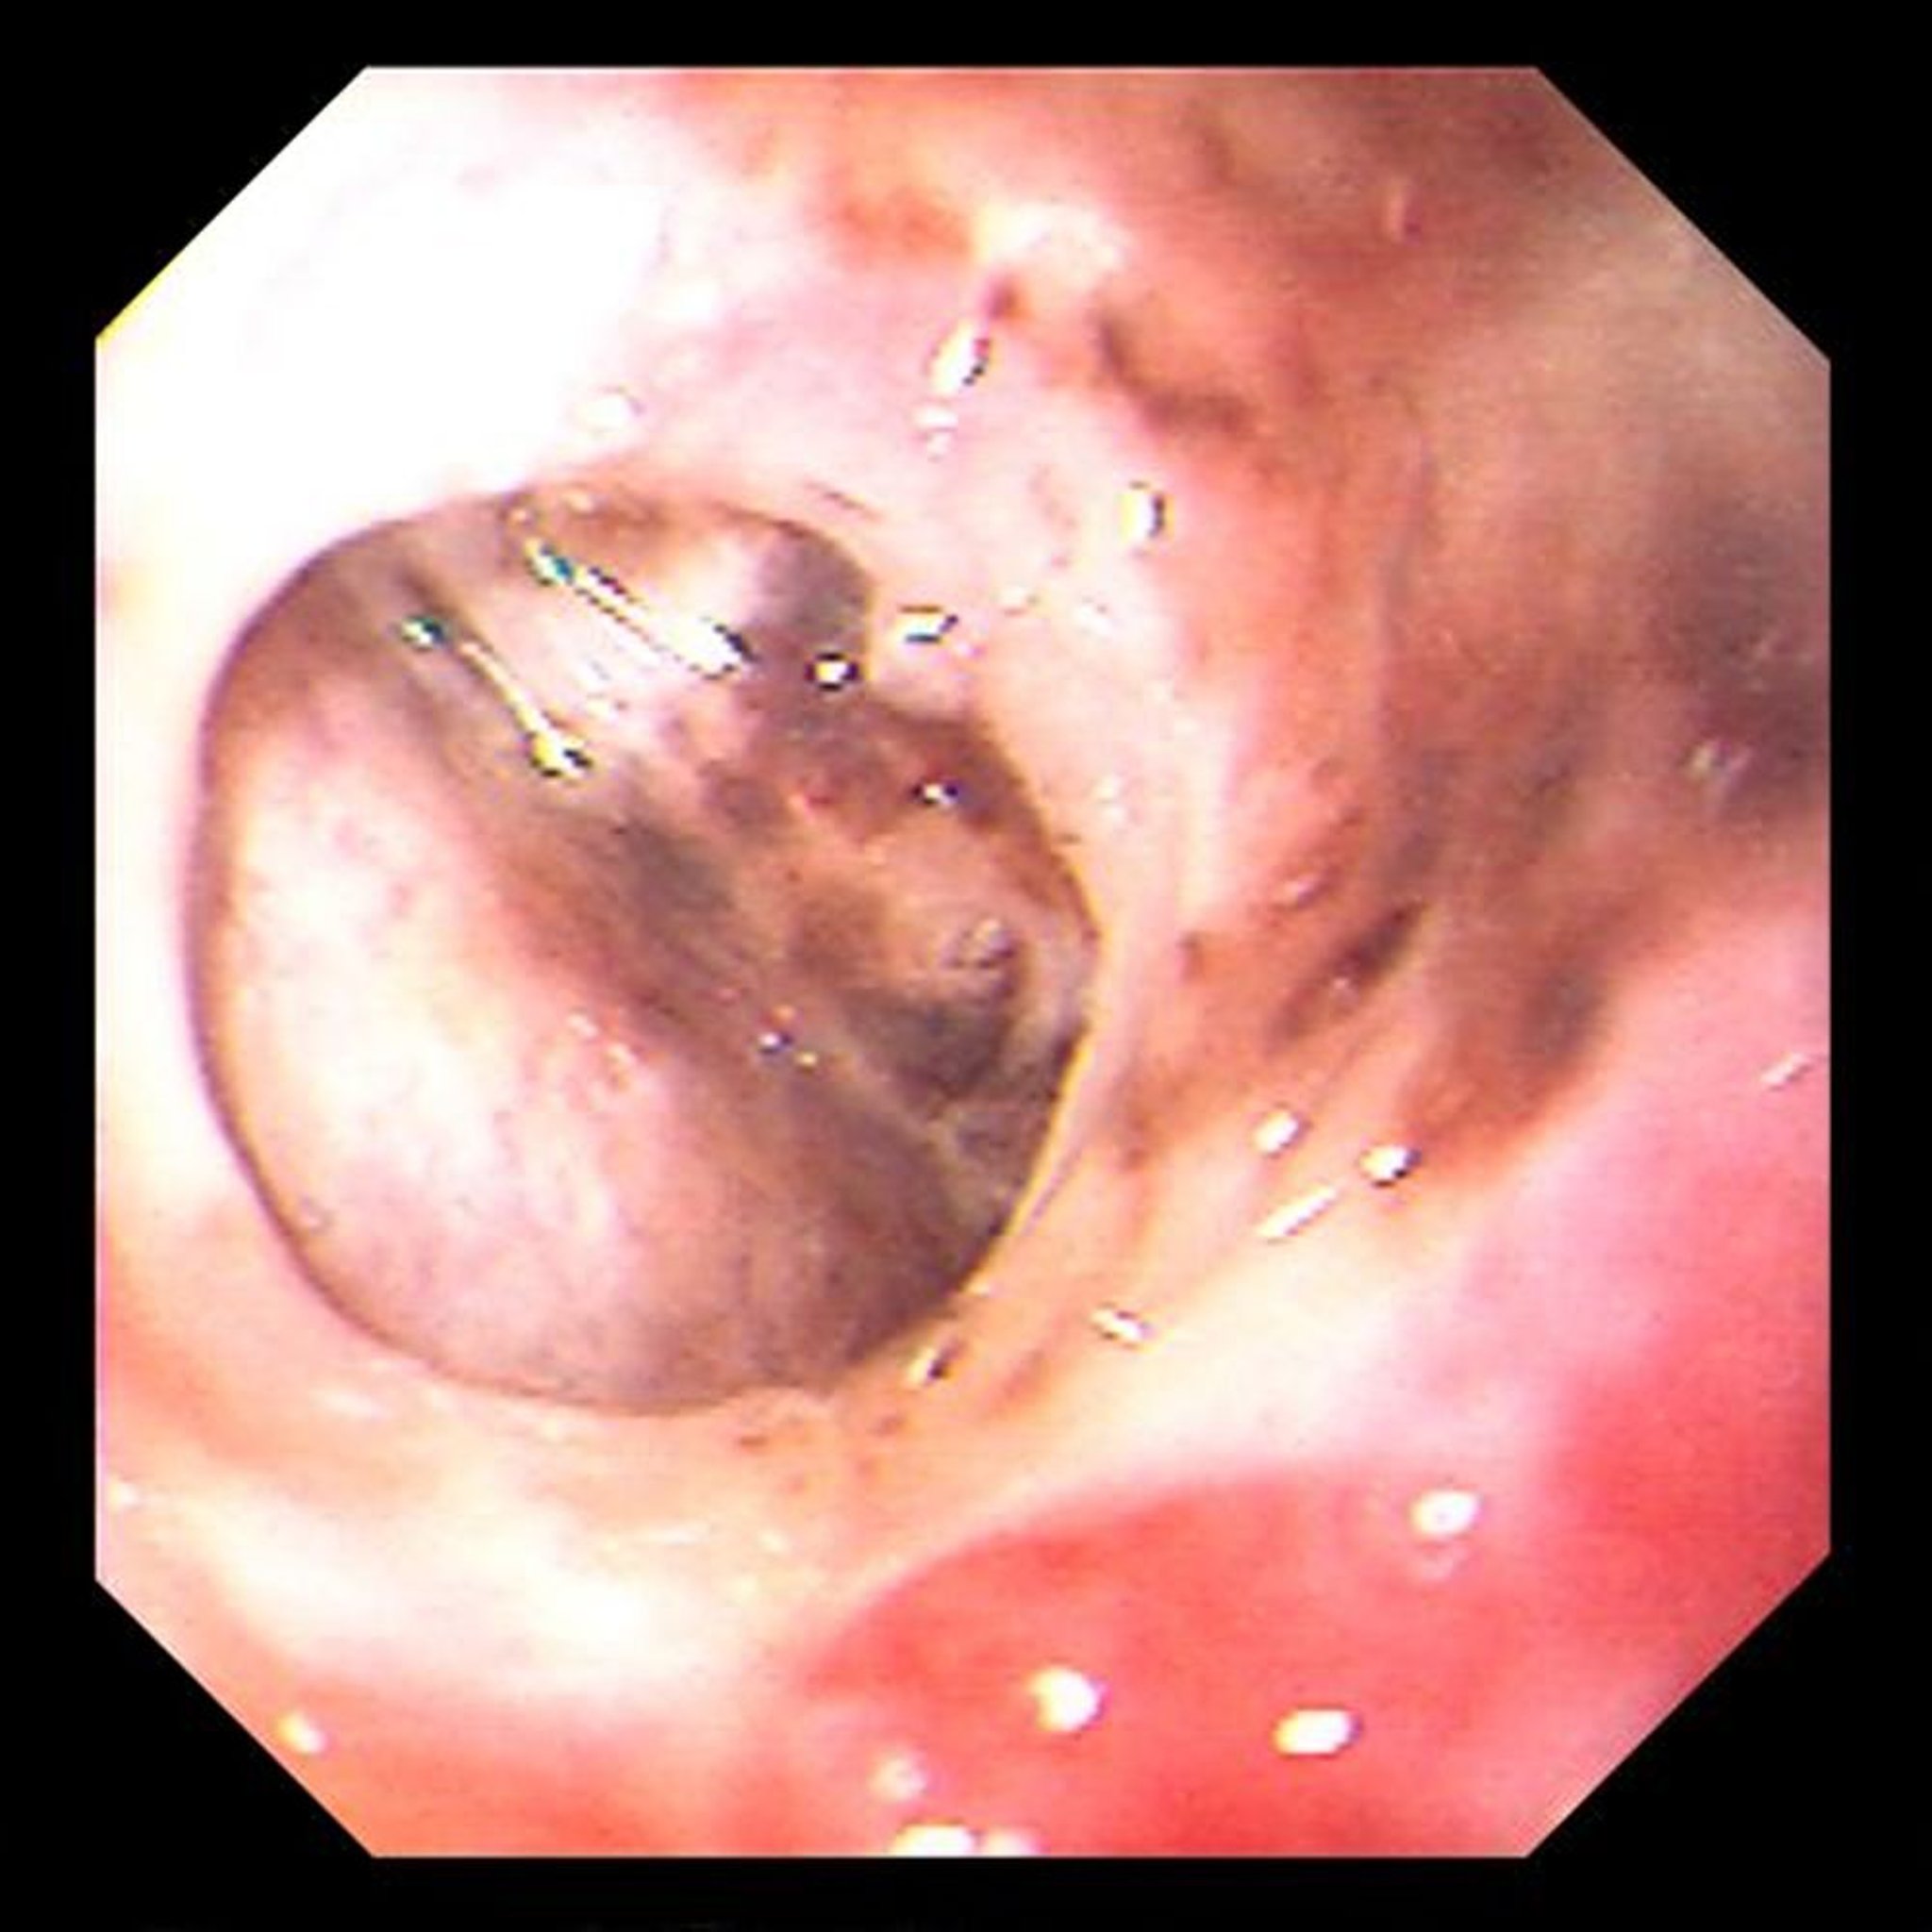

Thủng loét dạ dày

Hình ảnh này cho thấy vết thủng loét dạ dày mạn tính, giới hạn, qua đó có thể nhìn thấy gan.

Hình ảnh do bác sĩ David M. Martin cung cấp.